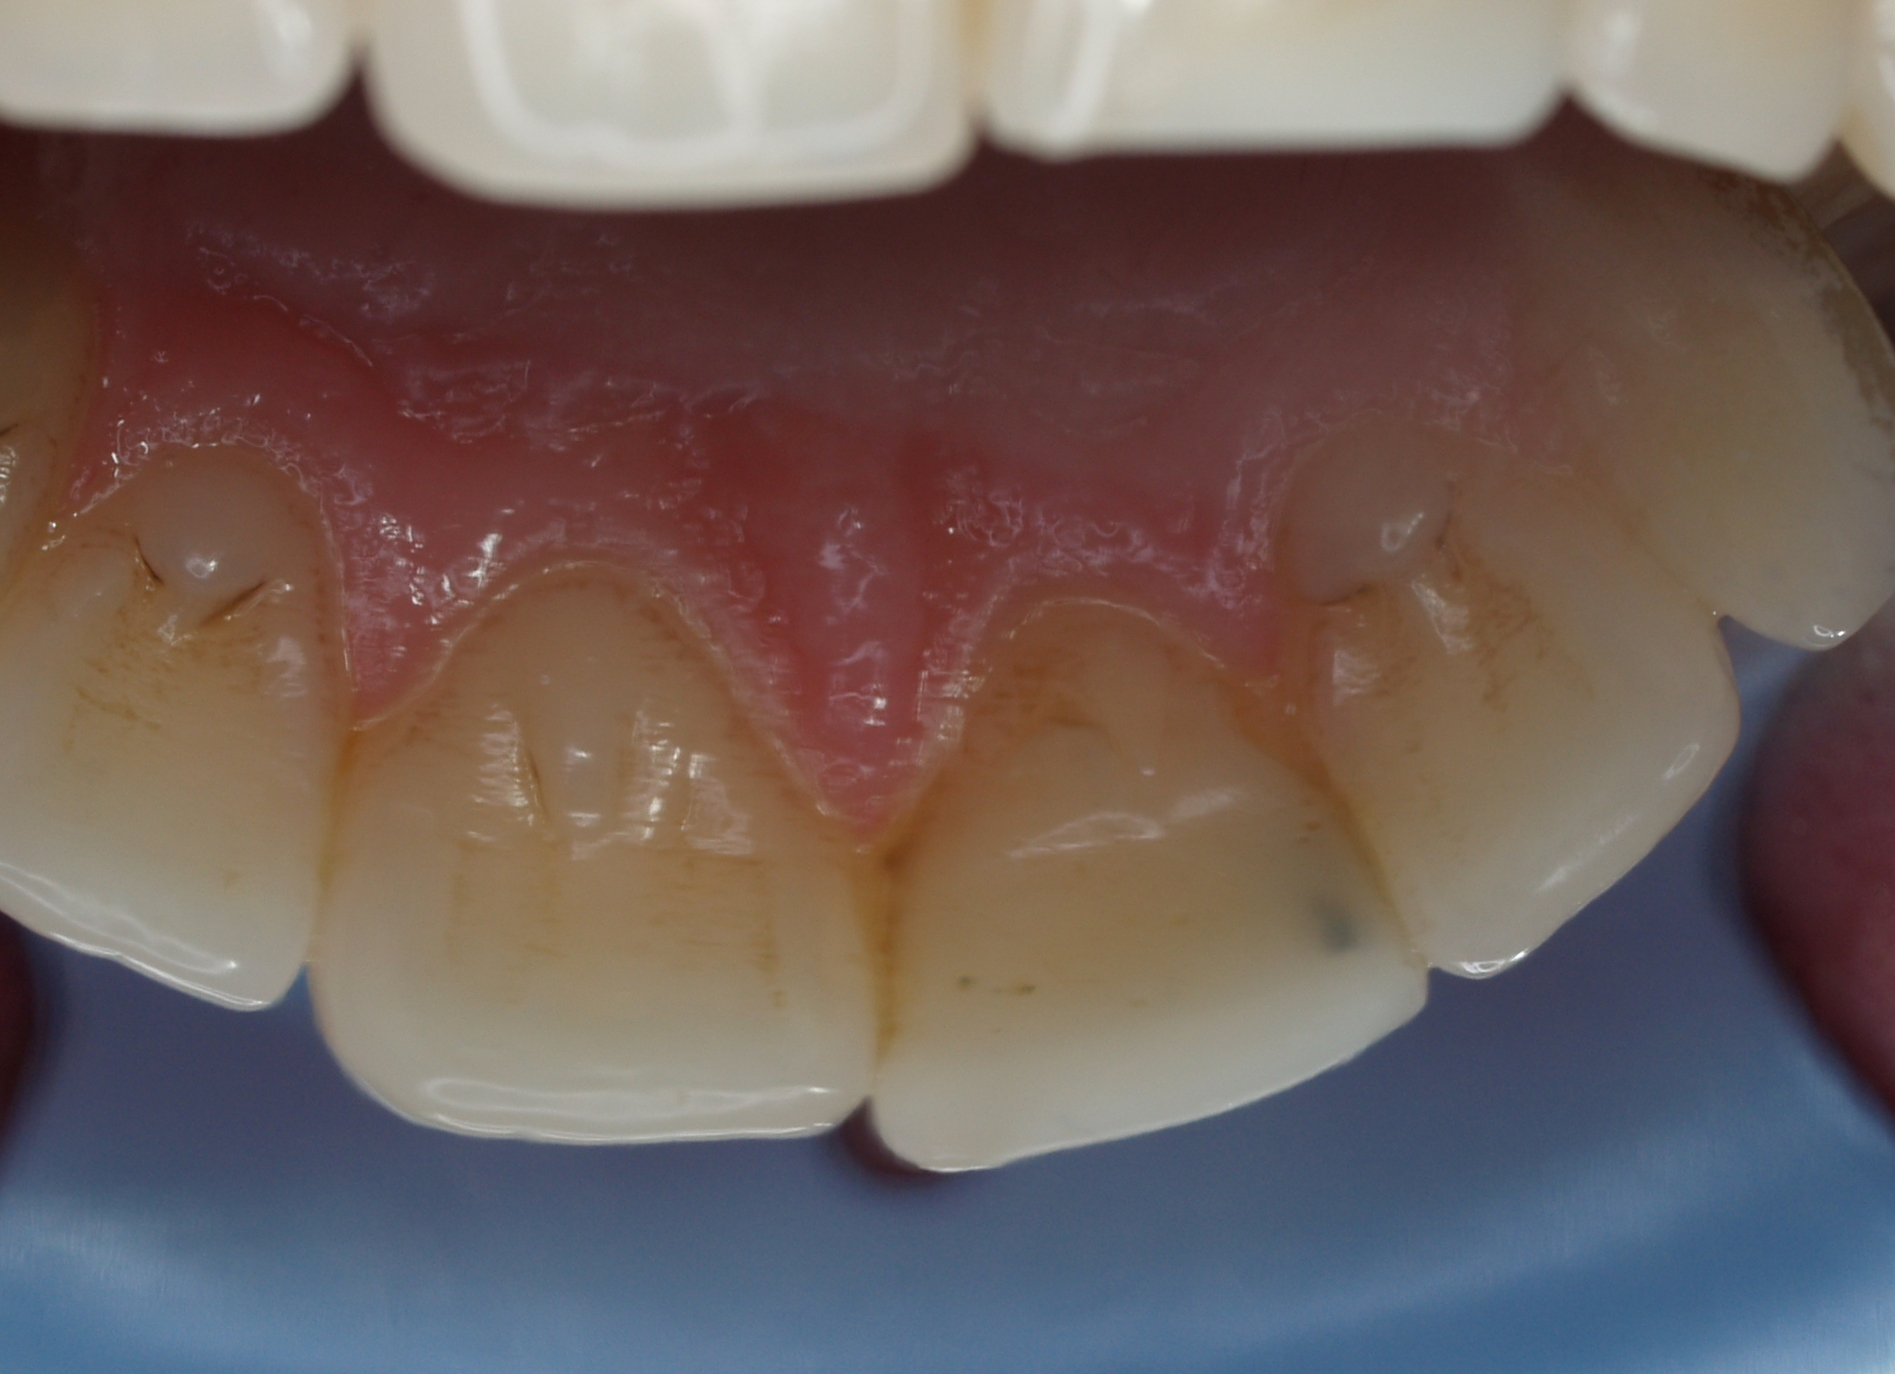

Nieestetyczne wypełnienie w zębie 21 skłoniło pacjentkę do jego wymiany. Podczas badania stwierdzono obecność ćwieka okołomiazgowego. W oparciu o ustalony kształt wypełnienia wykonano indeks silikonowy z materiału przezroczystego PempSpan™. Po usunięciu wypełnienia podjęto próbę usunięcia ćwieka. Niestety, ukręcił się u podstawy. Oceniając warunki kolorystyczne i ewentualne uszkodzenia, jakie mogą powstać podczas wywiercania zachowanego fragmentu, w porozumieniu z pacjentką odstąpiono od usuwania złamanego fragmentu. Na matrycy silikonowej odbudowano ścianę podniebienną, a w oparciu o pasek szkliwo powierzchni dystalnej. Następnie wymodelowano dwoma warstwami zębiny kształt jej wypustek – mamelonów. Warstwę zewnętrzną wymodelowano z masy szkliwnej, tworząc pewien nadmiar długości. Po polimeryzacji krążkami ostrożnie skorygowano długość brzegu siecznego i kształt powierzchni dalszej. Całość starannie wypolerowano. Efekt estetyczny został zaakceptowany przez pacjentkę.